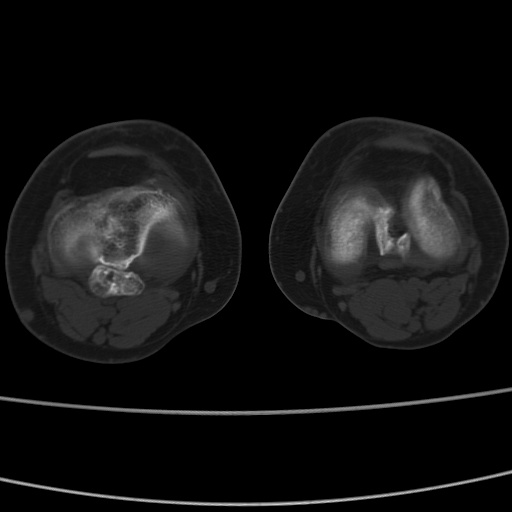

女性,50岁。【请提供患者临床症状体征】

右膝关节退行性改变,关节游离鼠。

右膝关节退行性改变,滑膜黏液囊钙/骨化并游离。

右膝关节退行性改变